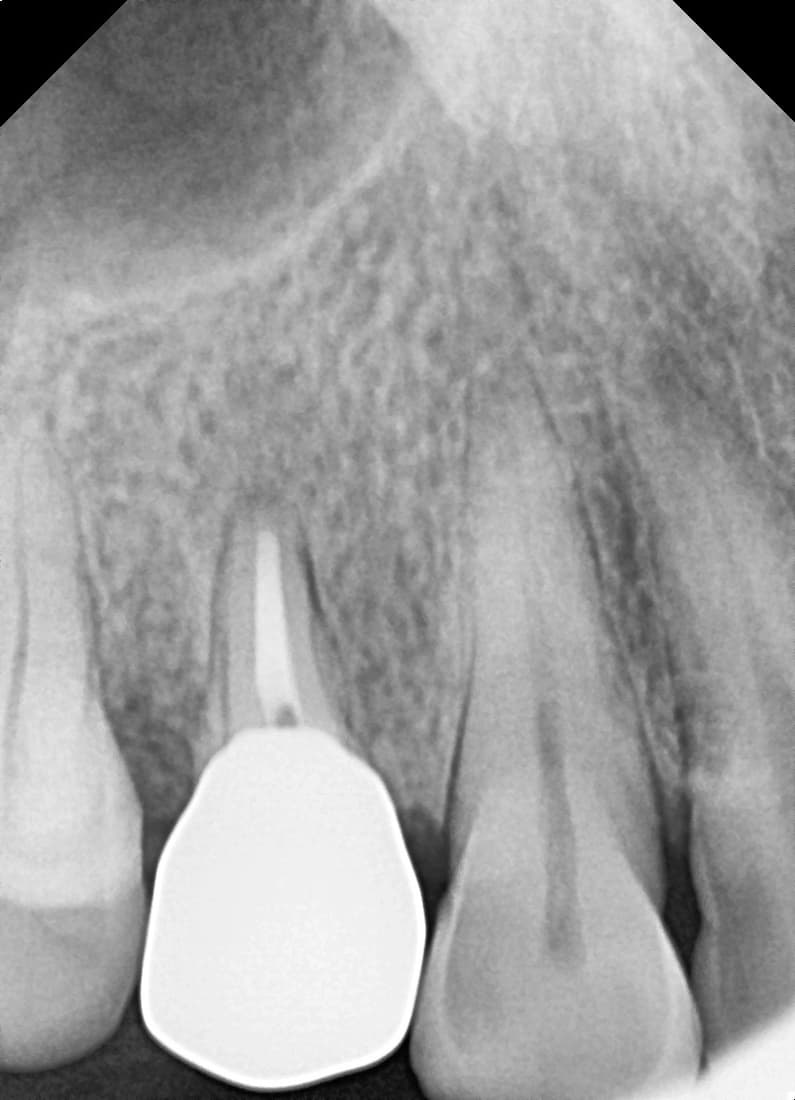

재신경치료

다른 병원 치료 후 재발한 어금니

Before

After

재신경치료로 추가 근관을 찾아 1년 9개월 후 완치